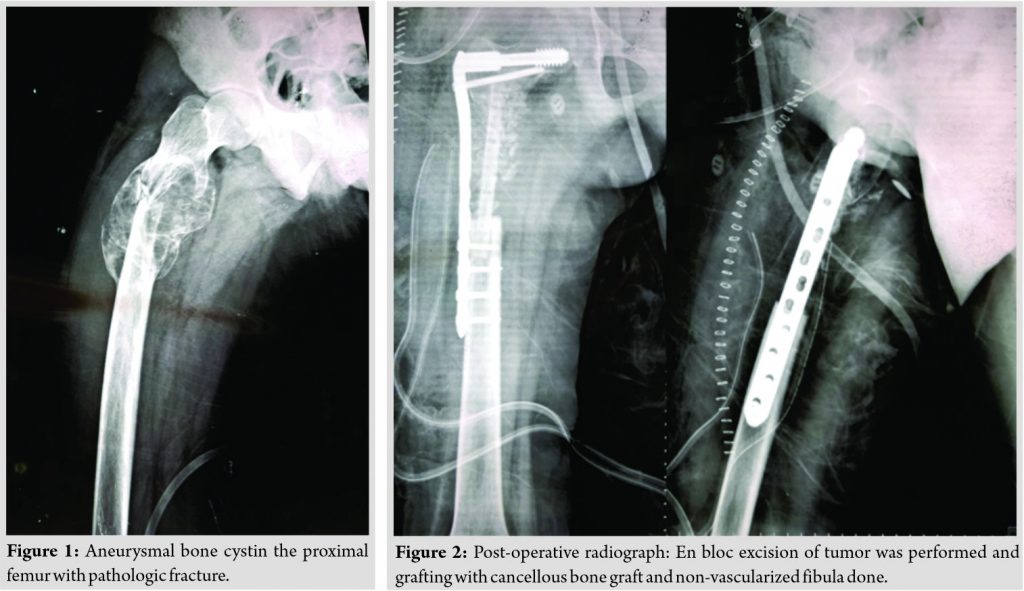

Case Report: We report a rare case of ABC with pathologic fracture in the proximal femur in a 15-year-old female patient, treated with en blocexcision, bone grafting with non-vascularized fibular strut graft and stabilized with a 95°dynamiccondylar screw plate system. Follow-up at 24 months showed incorporation of the fibular graft and full union.

We report a case of a 15-year-old girl who presented with pain in the right groin region following a history of trivial fall. She was unable to weight bear on the right side subsequently. She had an unremarkable medical and family history. Clinical examination revealed mild diffuse swelling of the right hip region with tenderness on deep palpation and restricted range of motion at the right hip joint. Skin overlying was normal without any redness or dilated veins. The patient was investigated and radiographs revealed a geographic lytic expansile lesion with septae with thin sclerotic margins involving the proximal metaphyseal region of the right femur along with pathologic fracture in the subtrochanteric region (Fig. 1). Magnetic resonance imaging also indicated the presence of an ABC in the proximal third of the right femur. Biopsy through the lateral approach confirmed the diagnosis of ABC. Selective arterial embolization was initially planned to devascularize the tumor, but lower limb angiogram revealed the tumor to be relatively avascular. A lateral approach to the tumor was performed and the lesion was excised en bloc with 1cm of normal bone on either end. The Richard screw was first passed into the femoral neck and head followed by wide excision of the tumor. It resulted in a gap of around 10 cm in the proximal femur. A non-vascularized fibula strut graft of 11 cm was harvested from the ipsilateral side and was augmented with cancellous autologous iliac bone graft. A dynamic condylar screw (DCS) plate system consisting of 8-hole titanium plate with distal four bicortical screws was used to stabilize it (Fig. 2).